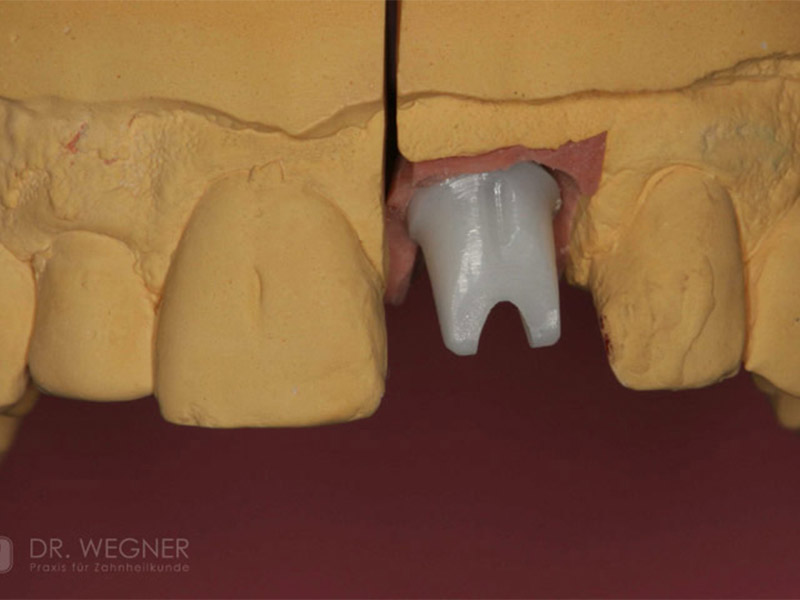

Zahnimplantate werden anhand von moderner virtueller 3D-Planung passgenau geplant und inseriert. Der Vorteil von Implantaten besteht darin, dass festsitzender ästhetischer Zahnersatz auch in solchen Fällen realisiert werden kann, in denen sonst nur herausnehmbare Prothesen möglich wären. Zudem ist im Gegensatz zur Brückenprothetik kein Beschleifen der Nachbarzähne notwendig.

Unter dentalen Implantaten versteht man im allgemeinen eine Schraube, die dort, wo ein oder mehrere Zähne verloren gegangen sind, in den Kieferknochen "eingepflanzt" wird. Diese Therapieform der Implantologie hat sich in den letzten Jahren zu einem alltäglichen Therapieverfahren in der Zahnheilkunde entwickelt. Wissenschaftliche Untersuchungen zeigen hierfür eine Erfolgsquote von i. d. R. 80-98 % über 10 Jahre. Verglichen mit anderen zahnärztlichen Maßnahmen gibt es nahezu keine andere Therapie mit derart guten Erfolgsaussichten. Auch eine Verbesserung der Lebensqualität wird durch implantatgetragenen Zahnersatz laut klinischer Studien erreicht.